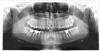

leoteo Опубликовано 9 февраля, 2013 Поделиться Опубликовано 9 февраля, 2013 Здравствуйте! У меня проблемы с правым нижним зубом мудрости. Воспалился капюшон, его срезали, гной откачали. После операции прошла неделя. Прикладываю рентген. Пожалуйста, скажите, нормально ли растет зуб, нет ли с ним проблем и нужно ли его удалять? Ссылка на комментарий

kriokov Опубликовано 9 февраля, 2013 Поделиться Опубликовано 9 февраля, 2013 удалил бы все восьмые, и нижний правый в том числе. Места в челюстях нет для нормального прорезывания и функции восьмерок 1 Ссылка на комментарий

IvanK Опубликовано 9 февраля, 2013 Поделиться Опубликовано 9 февраля, 2013 Тоже за удаление + консультация ортопеда, терапевта по поводу зубов : правая сторона низ 5,6,7, левая сторона низ 6 Ссылка на комментарий